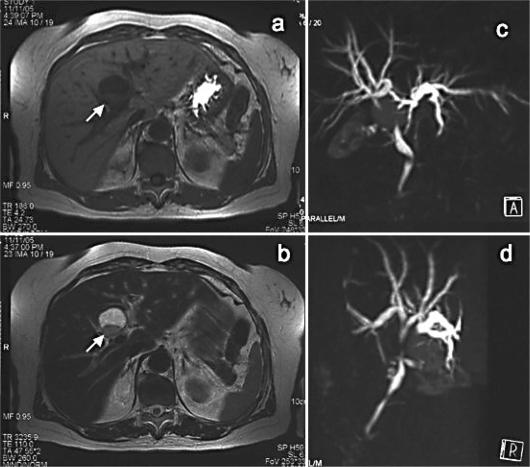

Ciliated hepatic foregut cysts (CHFCs) are rare congenital cystic lesion that are most often solitary, unilocular, and located in the subcapsular region of the medial segment of the left hepatic lobe. The mucoid fluid contents affect imaging studies and often make definitive diagnosis difficult. CHFCs are usually asymptomatic and found incidentally. We report a 69-year-old female patient with a CHFC causing obstructive jaundice, which was difficult to differentiate from a biliary cystic neoplasm. A well-defined cystic lesion measuring 25 mm in diameter was located in the porta hepatis region. The lesion was densely adherent to the left and right hepatic ducts, riding on the bifurcation, and the common hepatic duct was extrinsically compressed. An extended left hepatectomy was performed. A diagnosis of CHFC was made on the basis of typical histological findings. CHFC should be included in the differential diagnosis for cystic lesions of the liver.

纤毛性肝前肠囊肿(CHFCs)是一种罕见的先天性囊性病变,通常为单发、单房,位于左肝叶内侧段的包膜下区域。其黏液样内容物影响影像学检查,常使明确诊断困难。CHFCs通常无症状,多为偶然发现。我们报告一例69岁女性患者,其CHFC导致梗阻性黄疸,难以与胆管囊性肿瘤相鉴别。一个边界清晰、直径25mm的囊性病变位于肝门区。该病变与左右肝管紧密粘连,骑跨于肝门分叉处,肝总管受到外在压迫。遂行扩大左肝切除术。根据典型的组织学表现确诊为CHFC。CHFC应纳入肝脏囊性病变的鉴别诊断。